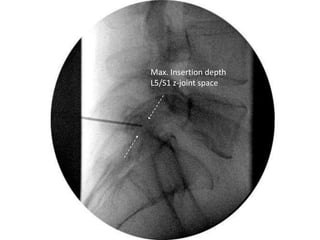

Max. Insertion depth

L5/S1 z-joint space

• 58.

Probe is 2mmoff bone for distal lesion projection